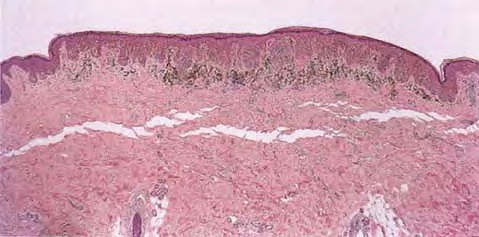

The lesions are usually 3 to 6 mm in diameter, deeply pigmented, and either flat or slightly raised. Most patients are young adults, and the most common location is on the lower extremities. Pigmented spindle cell nevi are uncommon after the age of 35 years. A classic presentation is that of a newly evolved black plaque on the thigh of a young woman. Because of the heavy pigment and the history of sudden appearance, a diagnosis of melanoma is often suspected clinically. In contrast, Spitz nevi are usually submitted with a benign clinical diagnosis, such as an angioma or a dermal nevus. Like Spitz nevi, the lesions are generally stable after a relatively sudden appearance and a short-lived period of growth. Histopathology. The pigmented spindle cell nevus is characterized by its relatively small size and its symmetry and by a proliferation of uniform, narrow, elongated, spindle-shaped, often heavily pigmented melanocytes at the dermal-epidermal junction . The nests of spindle cells are vertically oriented and tend to blend with adjacent keratinocytes rather than forming clefts as in Spitz nevi. Eosinophilic globules (Kamino bodies) may be present . The tumor cells often form bundles that are separated by elongated rete ridges. In the papillary dermis, the nevus cells lie in compact clusters, pushing the connective tissue aside. Numerous melanophages are characteristically diffusely present within the underlying papillary dermis. Involvement of the reticular dermis, common in Spitz nevi, is unusual in pigmented spindle cell nevus. Some lesions show upward epidermal extension of junctional nests of melanocytes. Single-cell upward invasion of the epidermis in a pagetoid pattern may be present but is usually not prominent . Features that may lead to a diagnosis qualified as atypical pigmented spindle cell nevus include architectural abnormalities including poor circumscription and pagetoid melanocytosis, prominent cytologic atypia, or a prominent epithelioid cell component . There may also be considerable overlap with dysplastic nevi . The significance of these atypical variants appears to lie in their greater chance of being misdiagnosed as melanoma because all reports of pigmented spindle cell nevi emphasize their benign behavior after excision. |